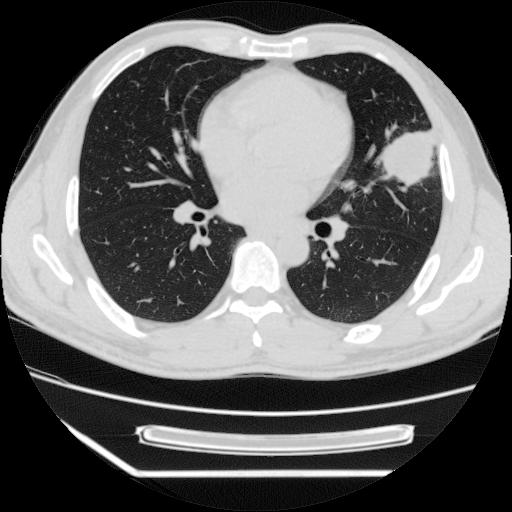

男,38岁,于2009年8月9日晚突发左侧胸痛,今x线提示左下肺阴影,为了明显确诊断,行ct检查,

病灶发生在下叶,密度均匀,边缘模糊、毛糙,周围血管纹理增强扭曲改变,靠近胸膜处病灶胸膜反应明显。

支持考虑---球形肺炎。

考虑左肺上叶舌段感染性病变(肺脓肿?);建议抗炎治疗后复查。

考虑左肺上叶舌段感染性病变(肺脓肿可能性大)。